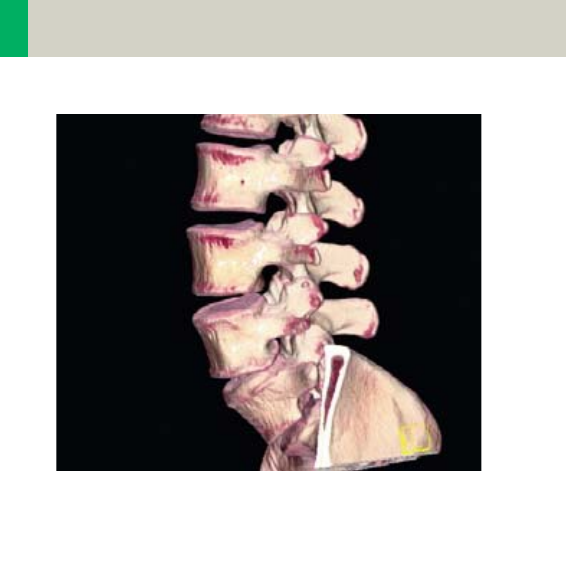

Spine 294

•Overview 294

- General Hints 296

- Body Kernels 297

•Scan Protocols 298

- C-Spine 298

- C-SpineVol 300

- SpineRoutine 302

- SpineThinSlice 304

- SpineVol 305

Contents

11

- SpineSeq 308

- Osteo 312